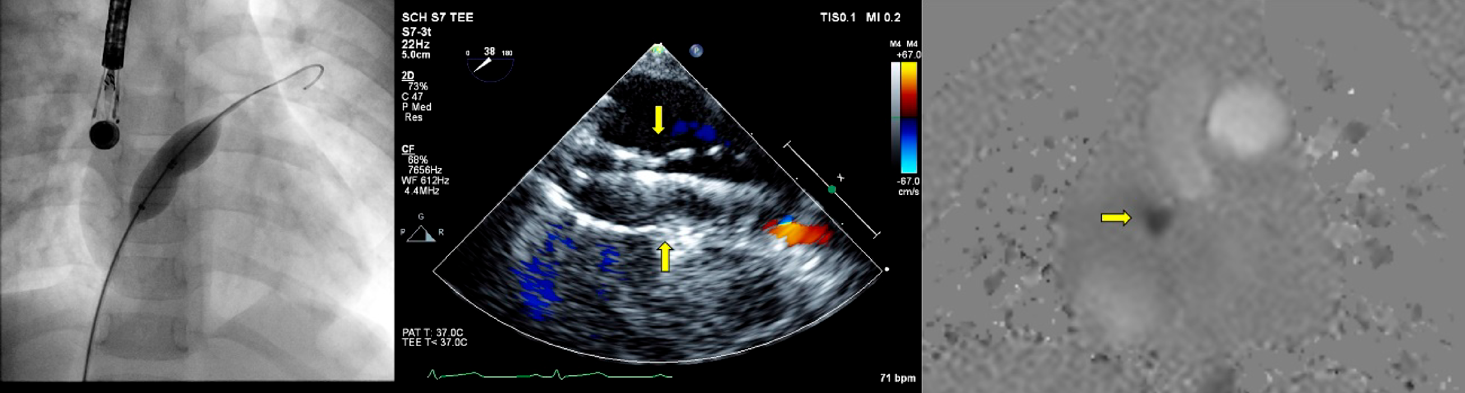

まず治療に先立ち経食道エコー(施設によっては血管内エコー)で,前述した欠損孔の解剖学的特性を把握する(Fig. 2).

Fig. 2 経食道心エコーでの欠損孔の観察

6歳児例.心臓MRIで体肺血流比1.7.経食道心エコーでの各角度での欠損孔の周辺縁(rim)の観察.前上縁欠損で,大動脈周囲縁が少ないが,その他の周囲縁(房室弁縁,後縁,後下縁,左房天井,上下大静脈縁,冠静脈洞縁,房室弁縁,肺静脈縁)は5 mm以上であった.